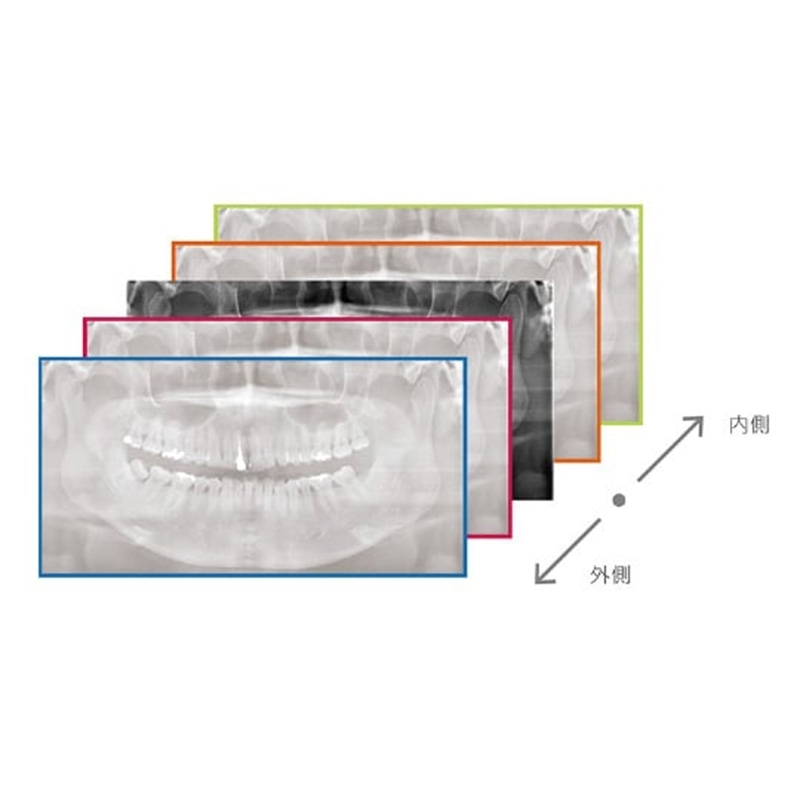

Information / DemoPanorama 2D

Veraview (IC5 HD) Spezifikationen

High-Speed-Modus - 5,5 Sek./192 µm

High-Definition Modus - 10 Sek./96 µm - Lichtvisiere: